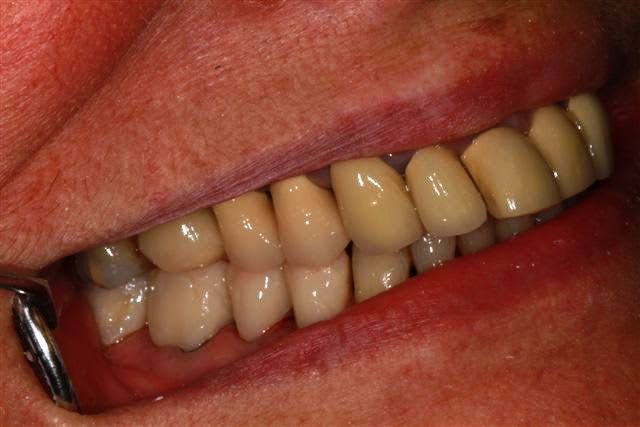

ce matin, grosse séance (4 h), pour le bas dépose des couronnes retraitement, taille et provisoires pour secteur 3 et 4 d'après le waxup, puis équilibration (le haut ne correspond pas encore), et bien désolé de te décevoir enlaye, mais les waxups donnent un résultat tip top...

secteur 3 et 4 ça avance,avec mes options pour l'occlusion, fonction du haut "chancelant", une fois le haut "stabilisé", je modifierais sans doute le bas.